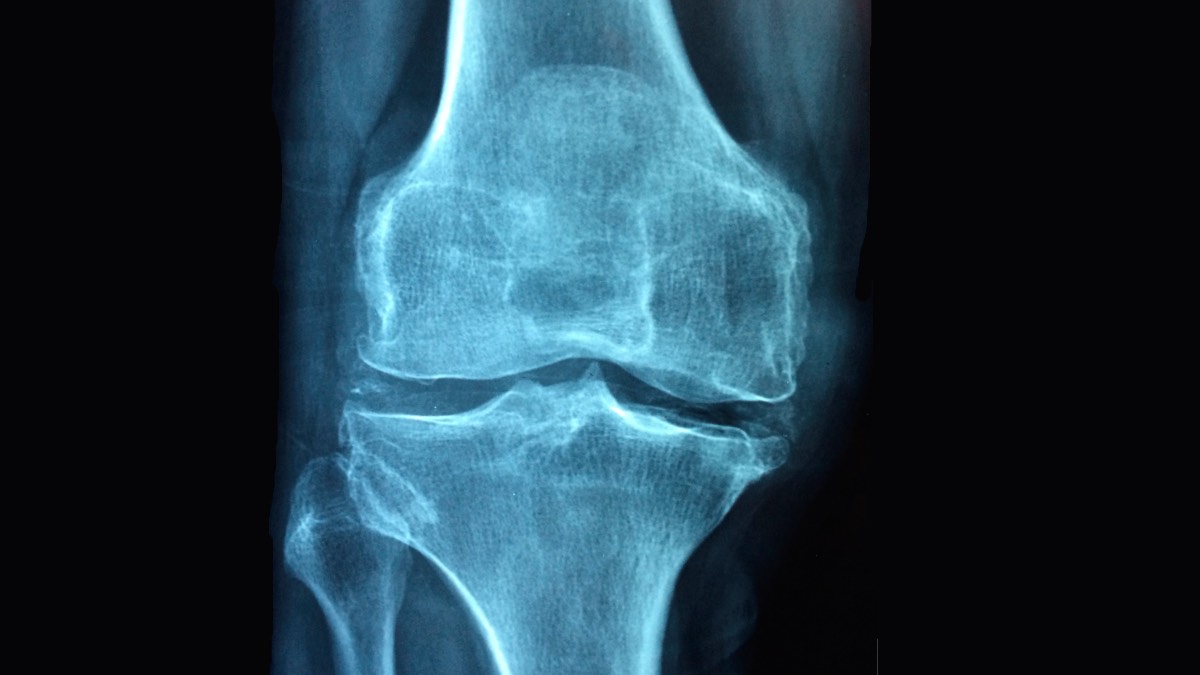

El diagnóstico de una meniscopatía es clave para tratarlo. Se confirma mediante un examen físico detallado y una resonancia magnética. Una vez identificada la lesión, la intervención quirúrgica puede ser necesaria, especialmente si el dolor y las limitaciones funcionales persisten.

Actualmente, la cirugía de menisco se realiza mayoritariamente con técnicas artroscópicas. Este procedimiento mínimamente invasivo permite reparar o extirpar el tejido dañado a través de pequeñas incisiones. "La artroscopia reduce significativamente los riesgos asociados a las cirugías tradicionales y permite una recuperación más rápida. En la mayoría de los casos, el paciente puede apoyar la pierna operada de inmediato y retomar sus actividades cotidianas en pocos días", explica Fernando Bascuñán, traumatólogo de Clínica Miguel Claro.